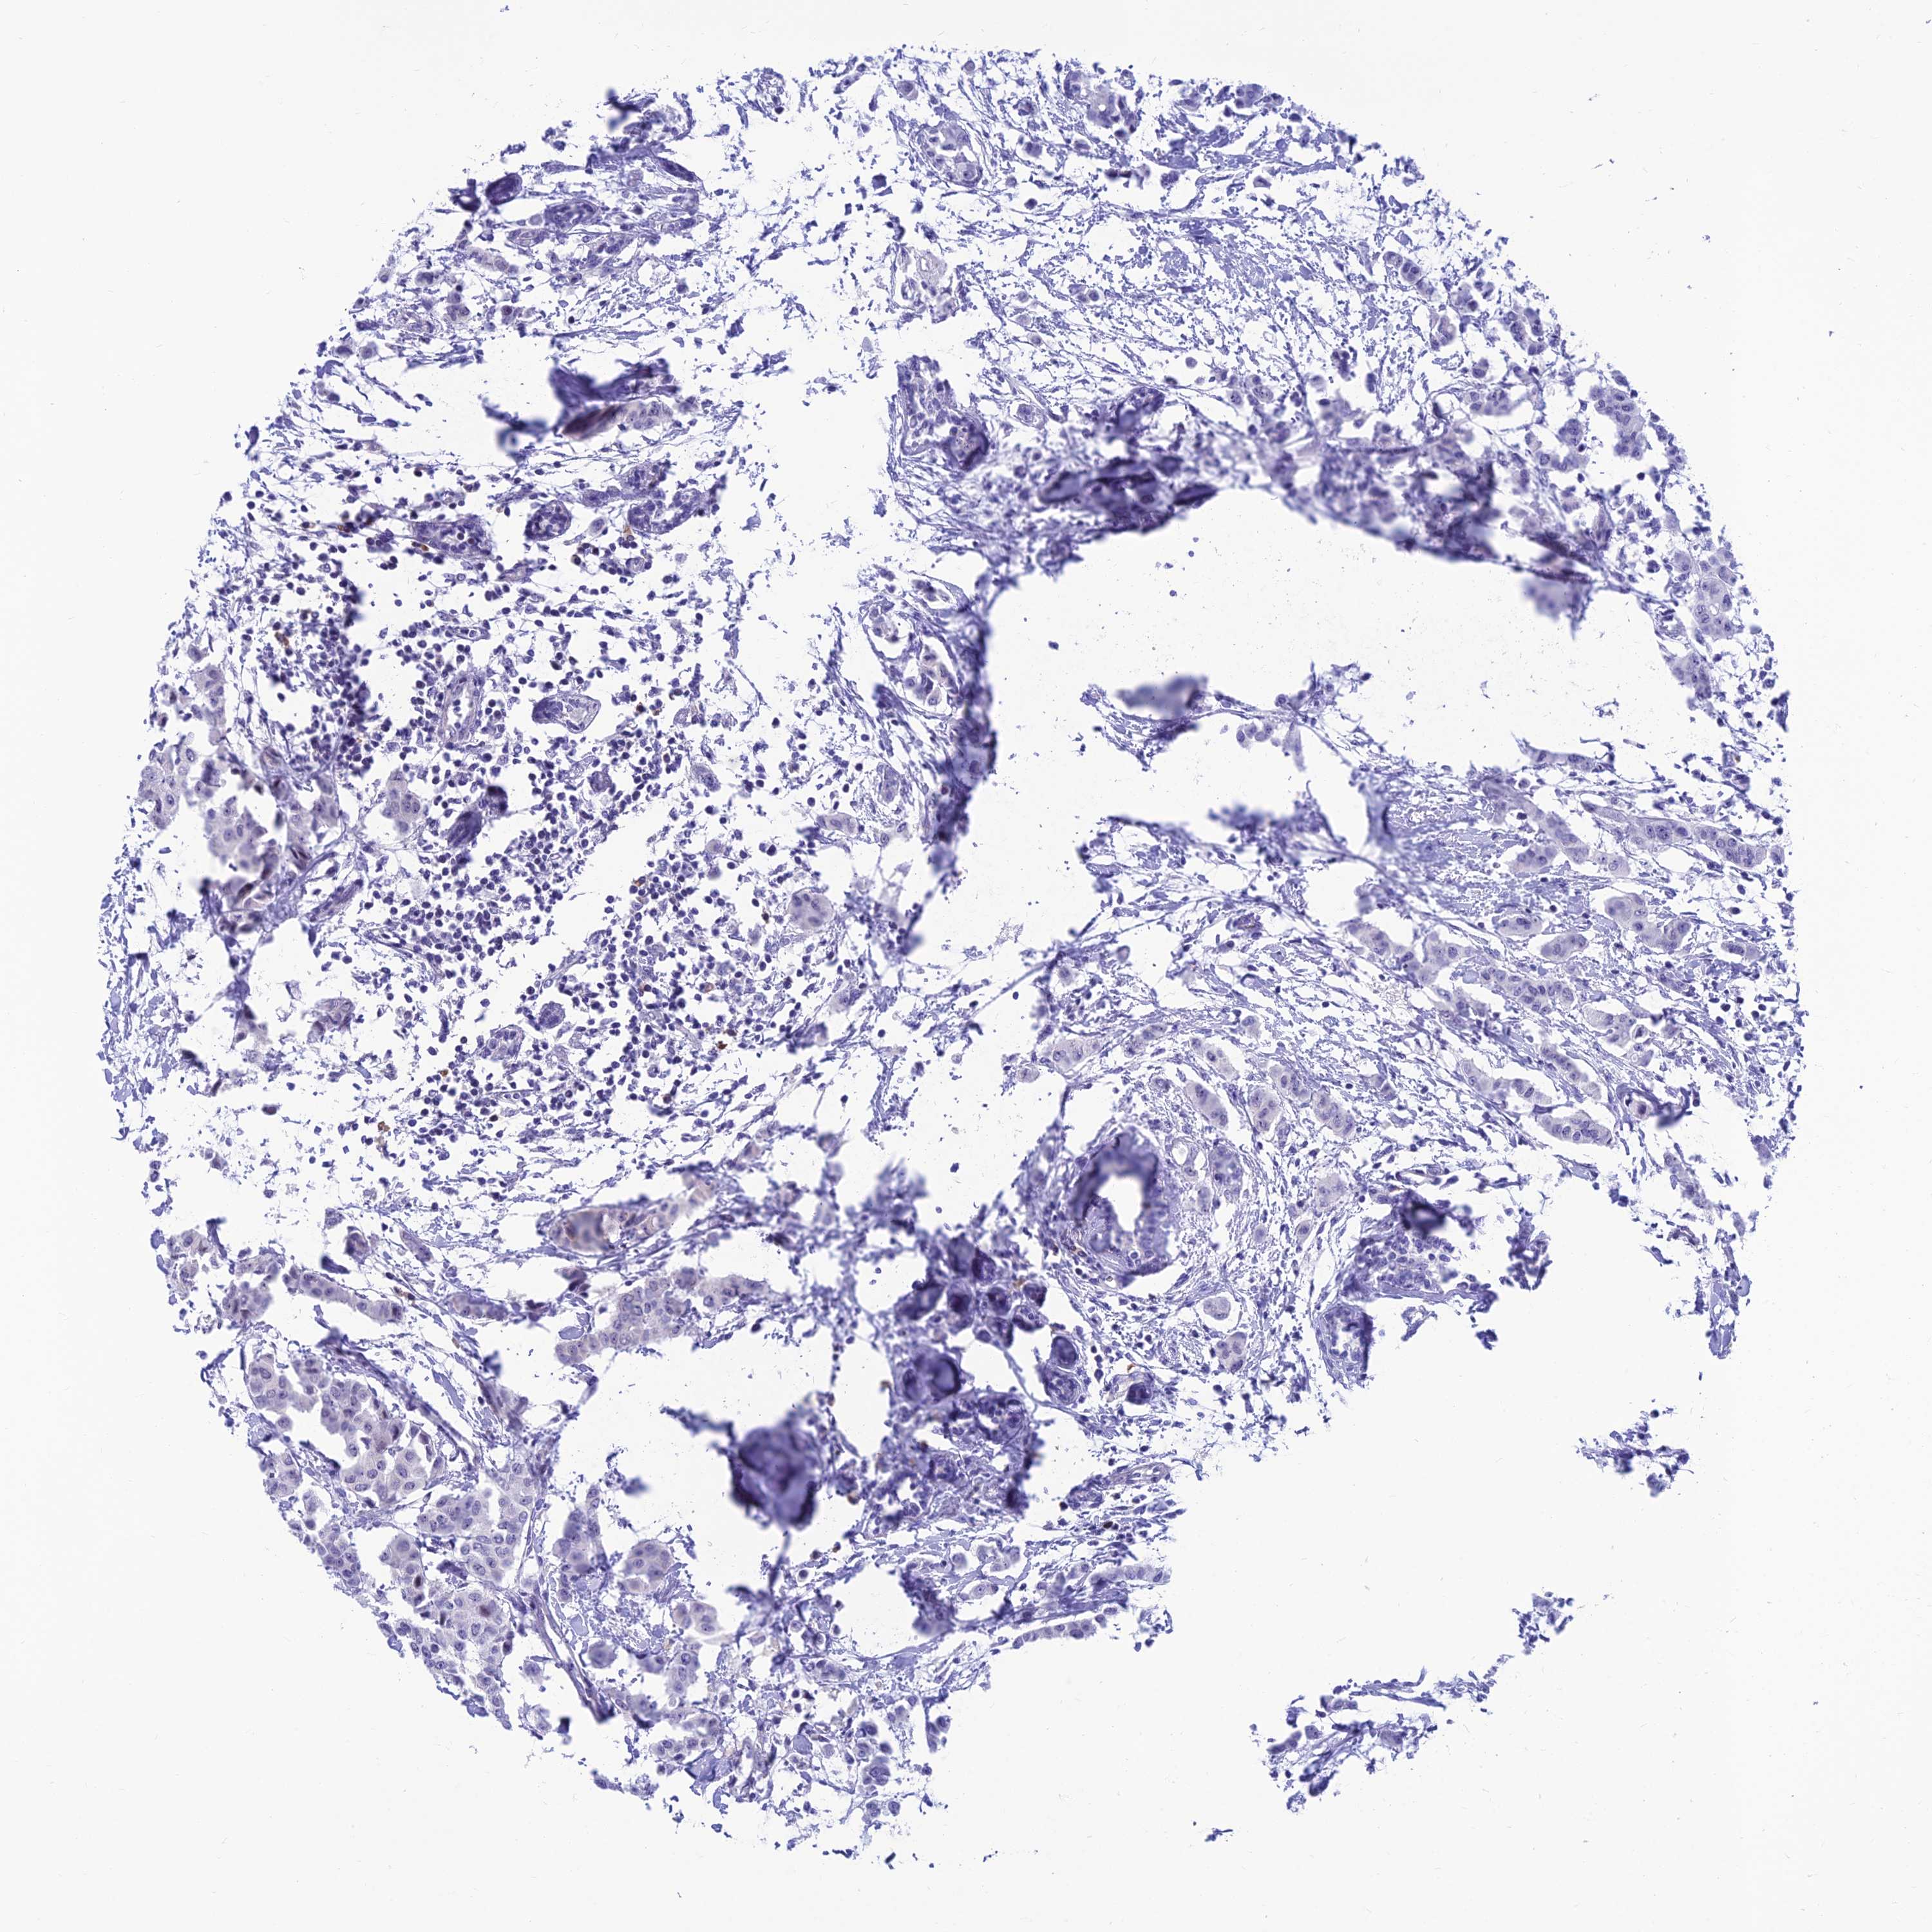

CANCER BREAST CANCER Show tissue menu

BRCA TCGA BRCA VALIDATION PROTEIN EXPRESSION

Breast cancer

Human cancer

Breast invasive carcinoma